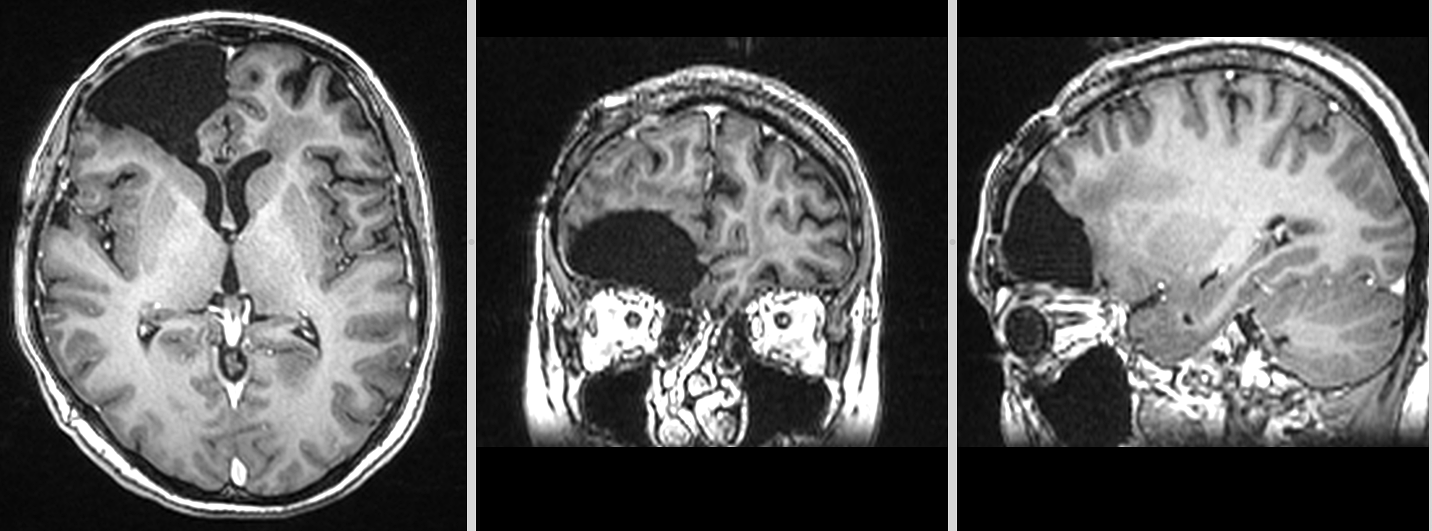

Totuși, la aproximativ 3 ani de la intervenția inițială, RMN-ul cerebral a evidențiat o modificare suspectă la nivelul zonei operate.

Aspectul nu era cel clasic de recidivă agresivă.

Leziunea avea caracteristici mai apropiate de un proces de tip low-grade, cu evoluție lentă și fără semne de agresivitate marcată.

Spectroscopia RMN a confirmat o progresie tumorală de tip low-grade, cu peak de colină (Cho) și N-acetil-aspartat (NAA).

În acest context, s-a decis reluarea tratamentului cu Temozolomidă.